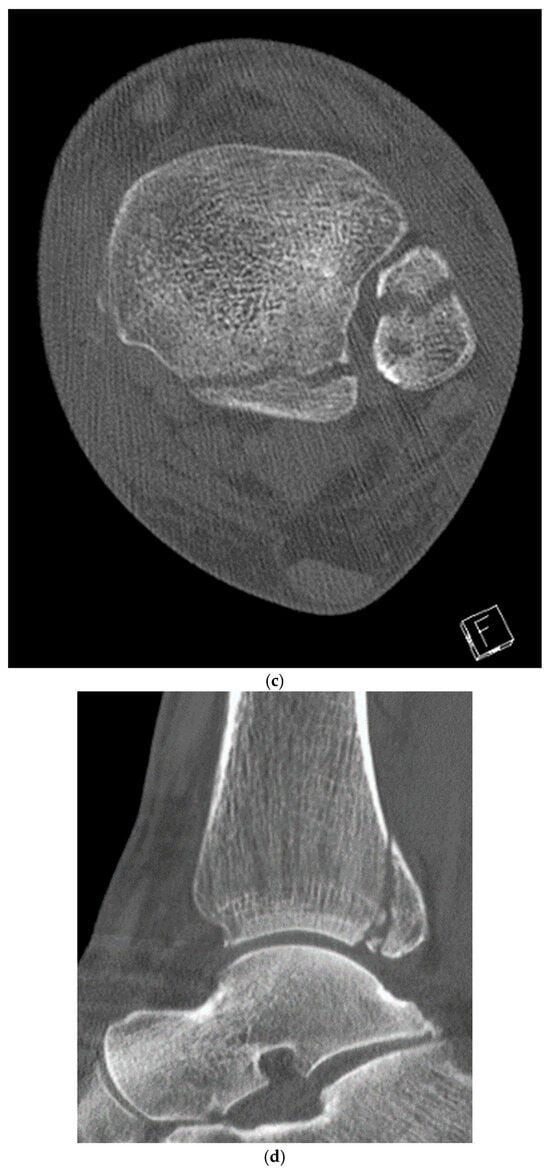

2. Preoperative Diagnostics

3. Intraoperative 3D Fluoroscopic Control

4. Classification

5. Case Description